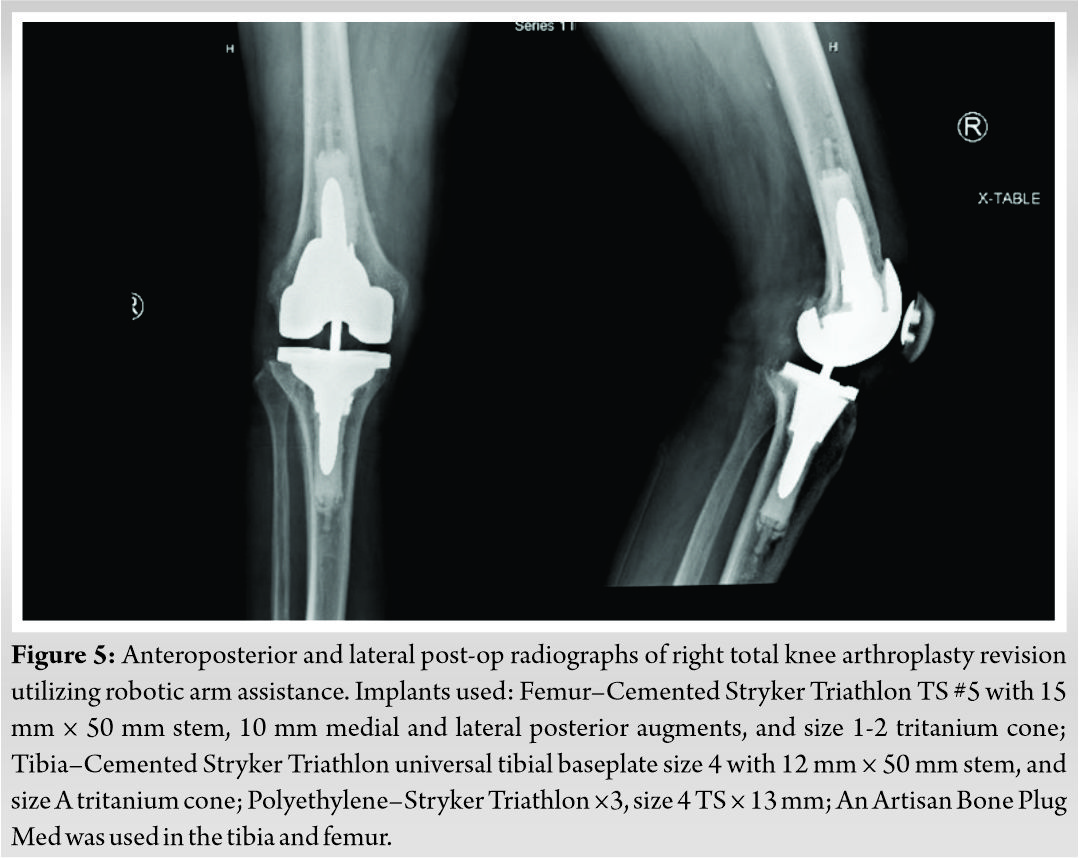

Case Report: We present a case describing a novel technique in which the Mako robot (Stryker, Ft. Lauderdale, FL) was utilized for revision of a failed primary TKA secondary to aseptic loosening. The patient is a 68-year-old Caucasian male who underwent right revision TKA with robotic assistance. Stryker Triathlon TS implants were utilized with the use of both femoral and tibial cones and medial and lateral posterior femoral augments. He had satisfactory component alignment based on postoperative radiographs, and excellent clinical outcomes 6 months postoperatively.

An intramedullary tibial alignment rod was used for centering the conical reamer in the tibia, and this was reamed to a size A cone. The TS femoral box cuts were performed, and conical reaming was again performed over an intramedullary guide on the femur to a size 1-2 cone. Trial components were then inserted and the knee was found to balance very well with a 13 mm trial polyethylene insert. All remaining cement was then removed from the bone surfaces, and remaining osteophytes were removed from around the patella. The joint was copiously irrigated with Irrisept (Irrimax Corp, Gainseville, FL) and normal saline. The tibial and femoral components were then cemented into place. A 13 mm polyethylene insert was used and the knee balanced quite well in full extension, mid flexion, and flexion to 90 degrees. The knee ranged from 0 to 135 degrees and had smooth and centered patellar tracking. Post-operative AP and lateral radiographs can be seen in fig5.

To the knowledge of the authors, this is the first case report to describe the use of robotic arm assist for revision of a failed primary TKA. The surgeon (AK) elected to use Mako technology and a Stryker Triathlon knee revision system. The patient had acceptable radiographic outcomes as assessed on postoperative radiographs by the authors, and the patient had excellent clinical outcomes 6 months postoperatively, with no complaints of knee pain, instability events, or stiffness. The use of robotic technology in rTKA for failed primary TKA is a new technique, and further study should be done to verify its use.